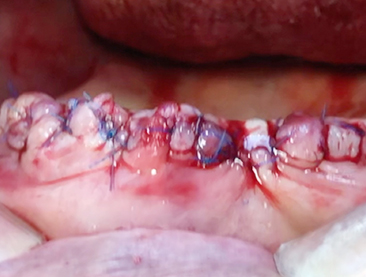

• Alveoloplasty (Posterior teeth) 4